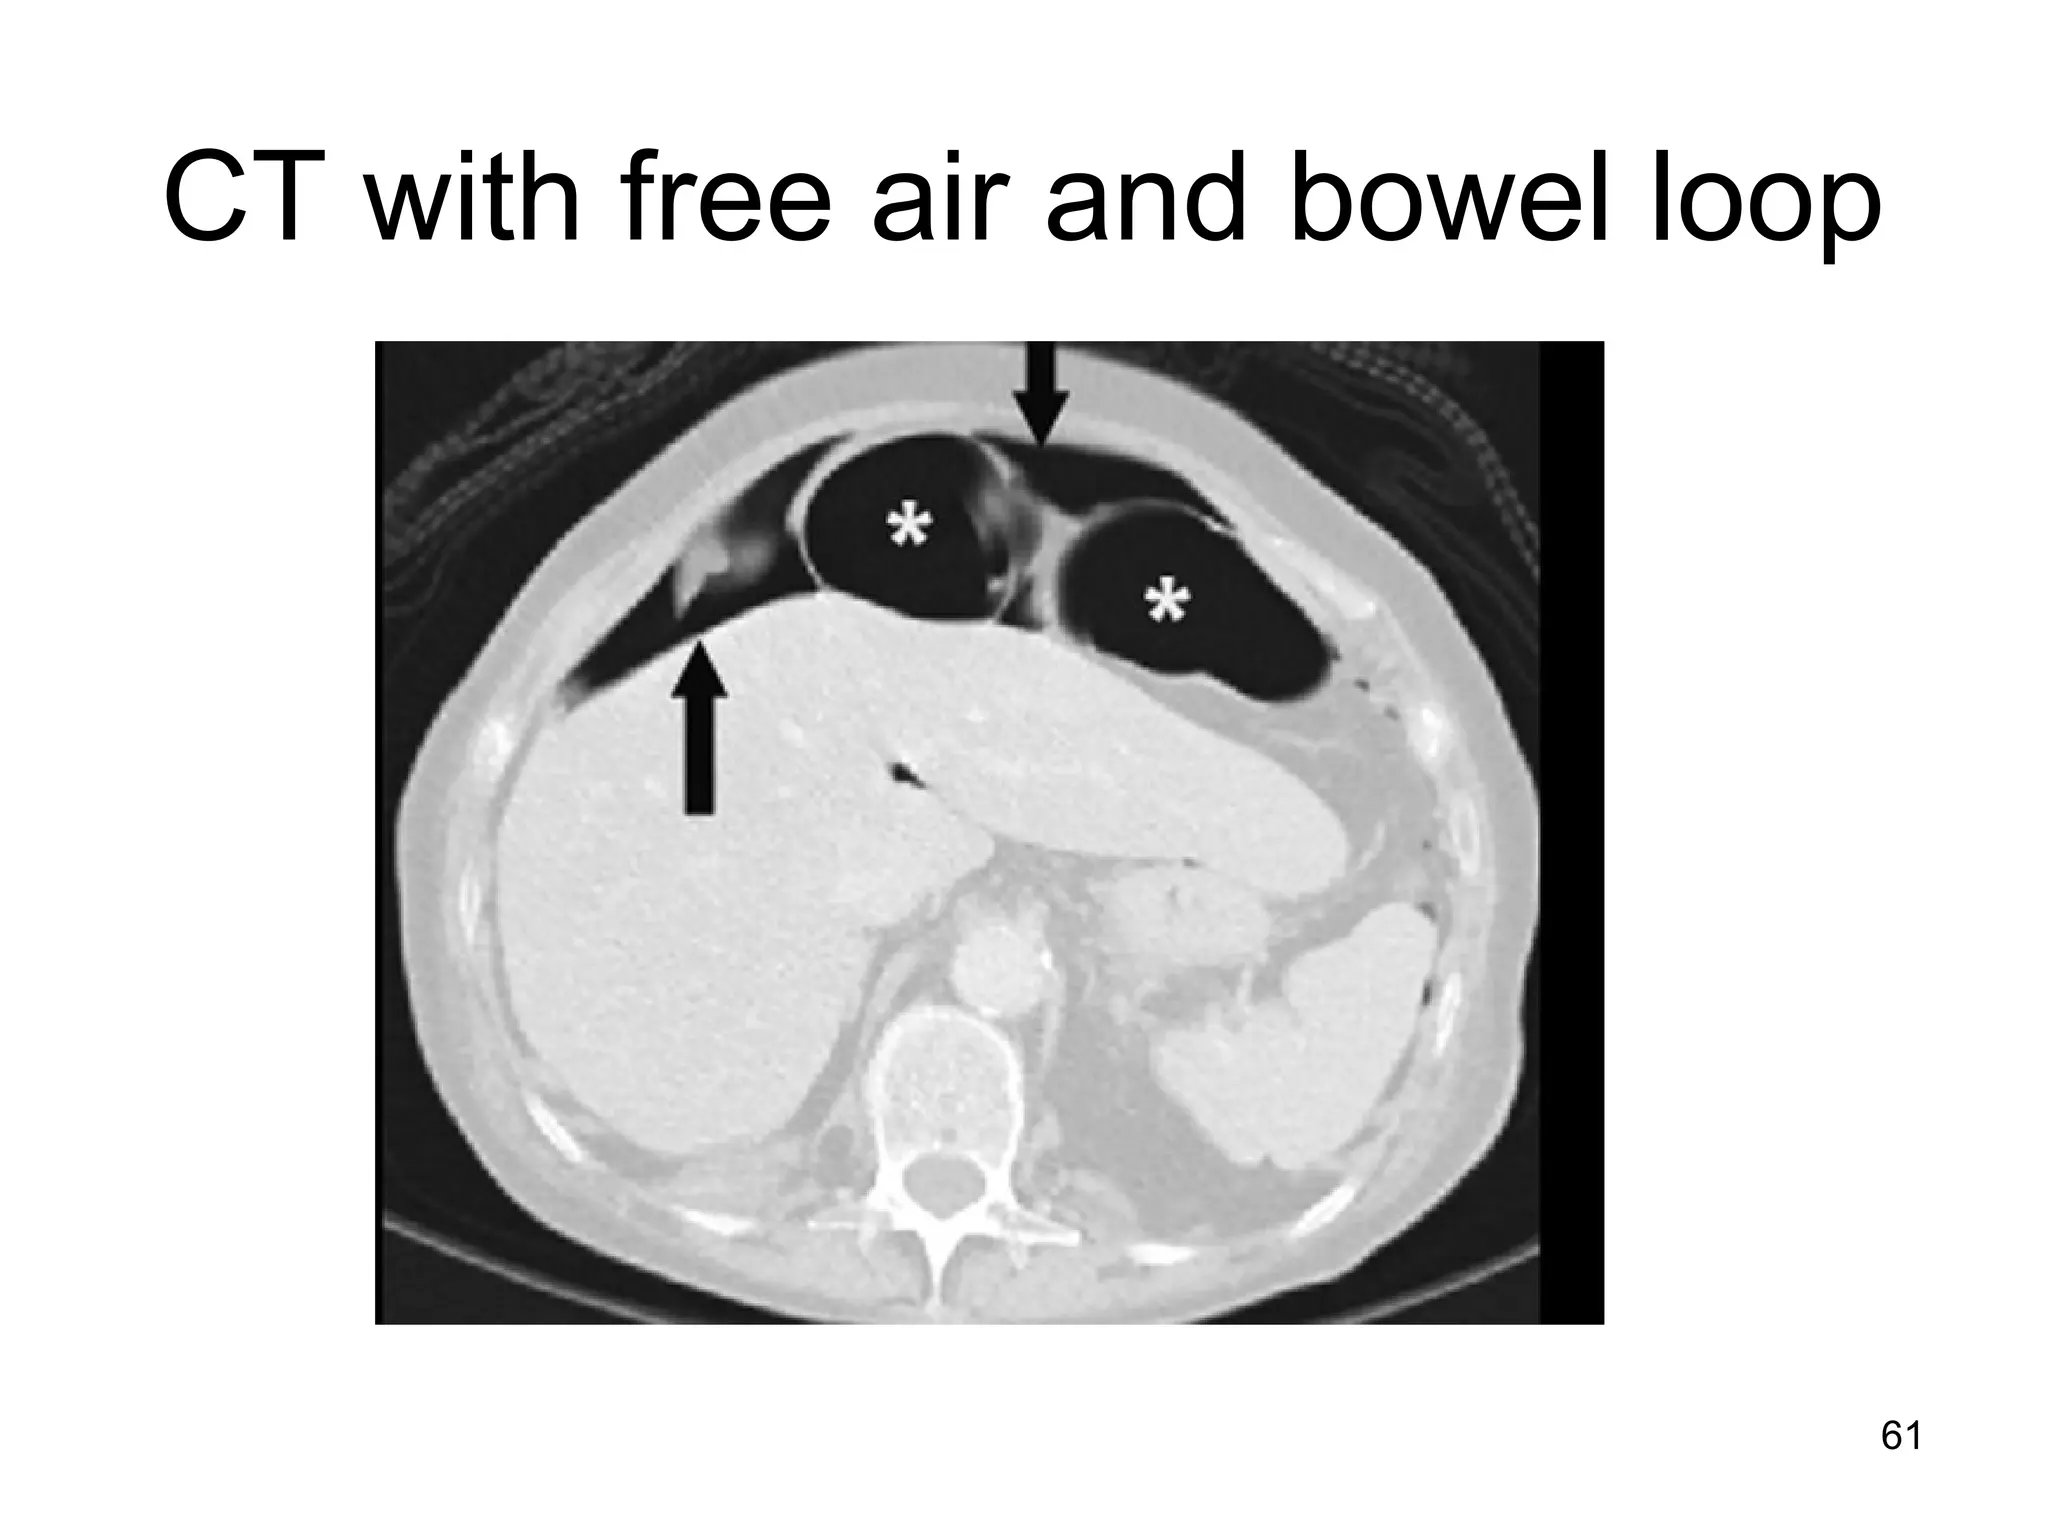

61

CT with free air and bowel loop